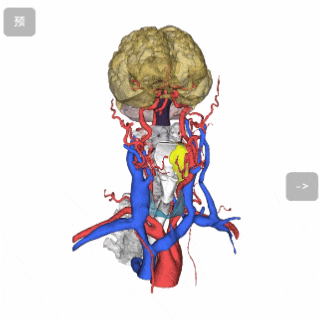

(根据CT图像,重建了肿瘤、动脉、静脉、大脑、小脑、甲状腺、骨骼、气管、神经等模型)

三维重建头颈系统动静脉整体预览

三维重头颈系统整体预览

头颈病灶切除分析